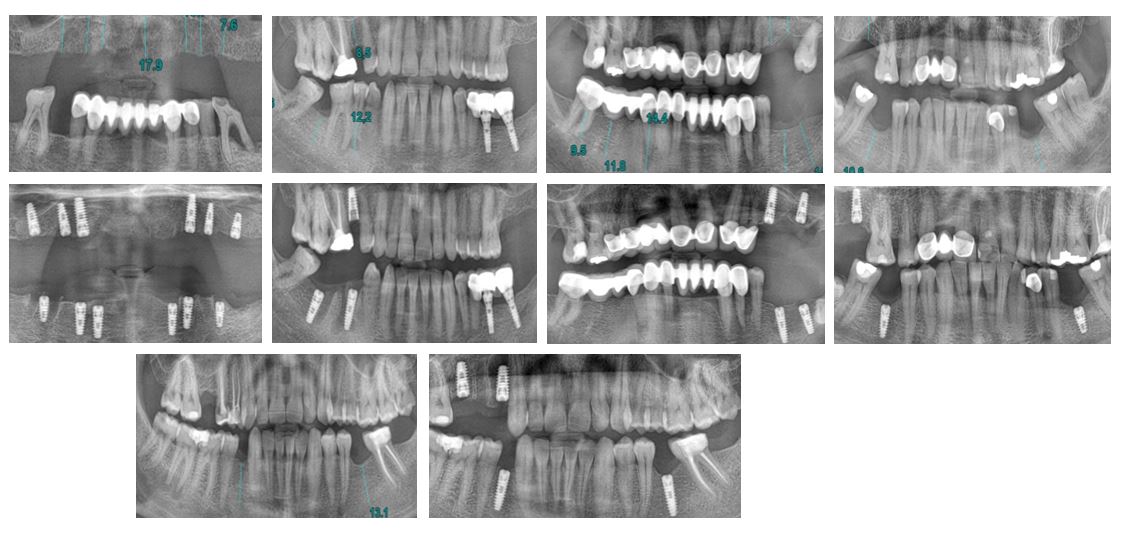

Bölge 2430 Diş Sağlığı Bölge Ana Komitesi’nden sağlanan implant desteği ve Bölge 2430 Şehit ve Gazilerimiz Bölge Ana Komitesi’nin yönlendirmeleri ile 4 Şehit yakını ve 1 Gazimizin ücretsiz 26 implantlık tedavisi yapılmıştır. Proje kapsamında Dönem Başkanı Necmettin Yeta ve Eşi Naz’ın kliniği DentPro’da gerçekleşen tedaviler muayene, ölçüm, işlem, kontrol adımları ile hasta başına 4 klinik ziyareti olmak üzere toplamda 1 ay sürmüştür.